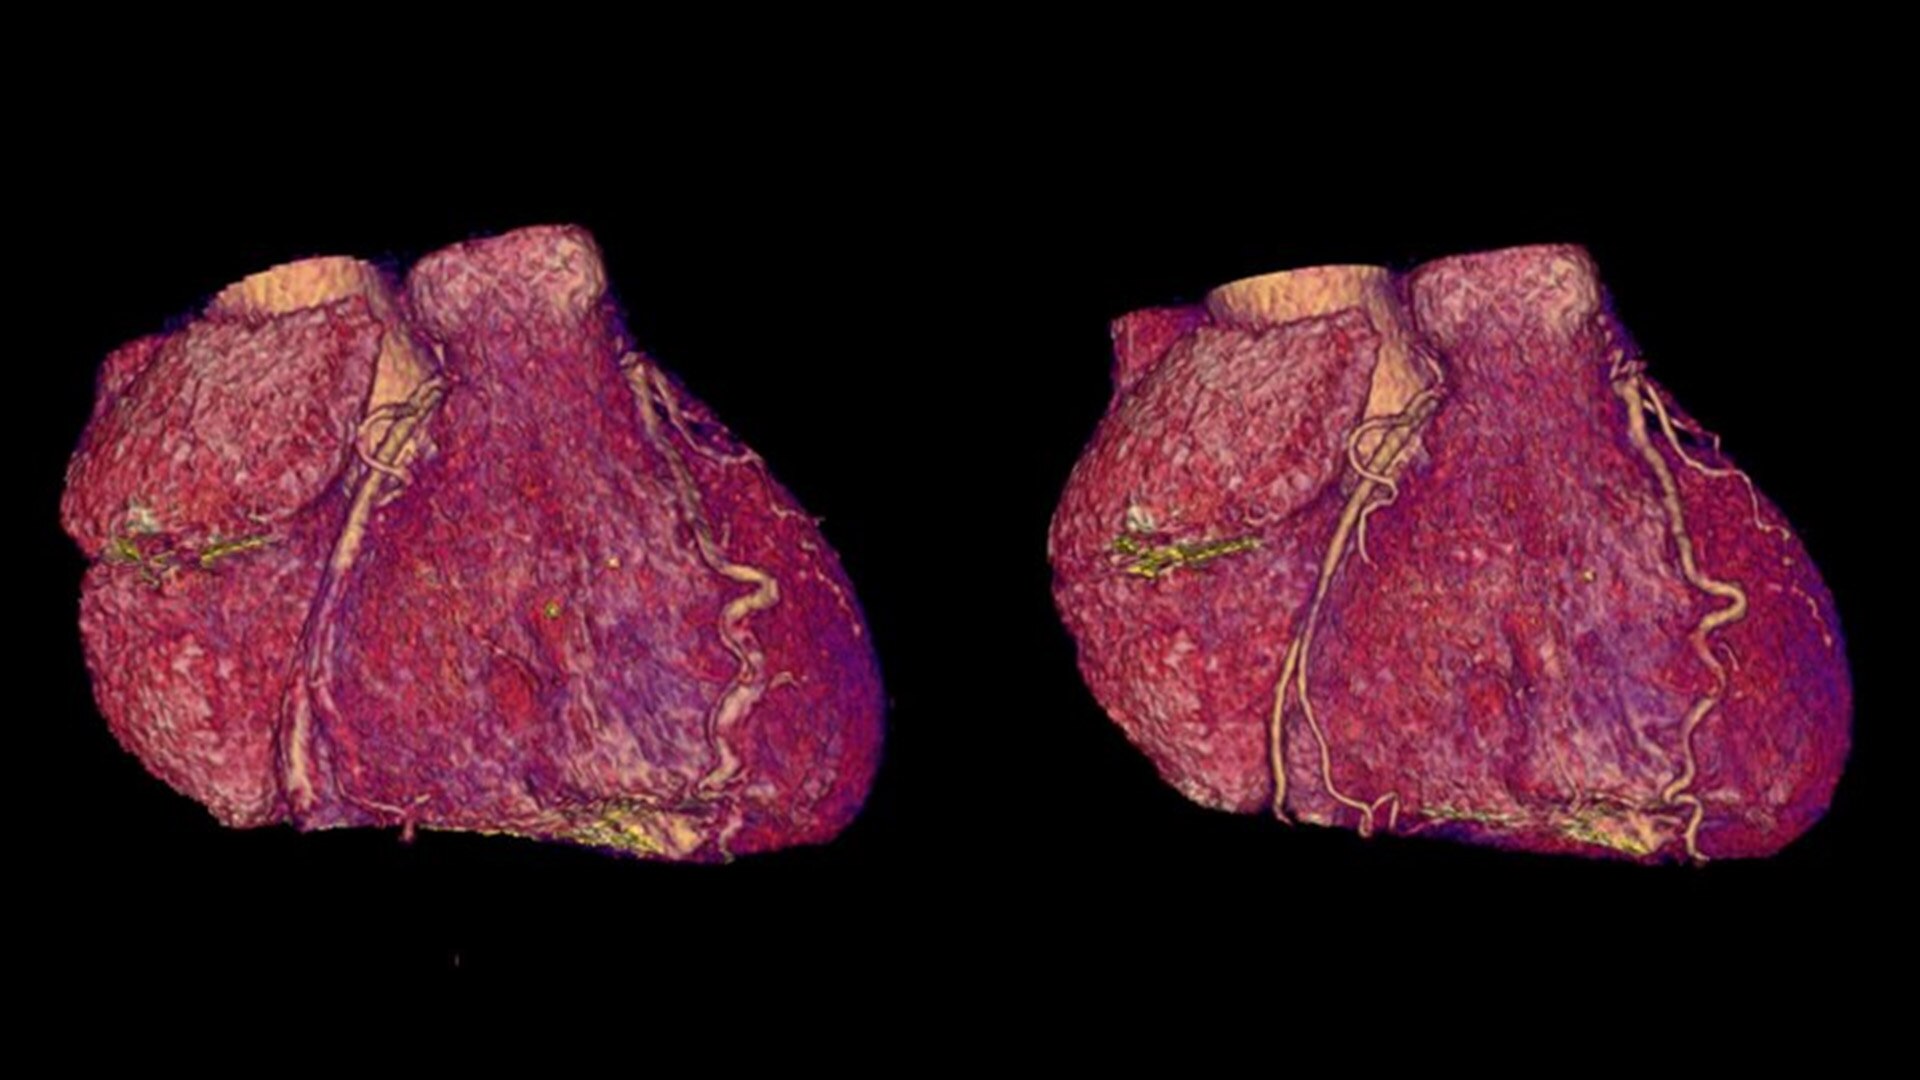

SnapShot Freeze 2

Intelligent and automated whole-heart motion correction for enhanced Cardiac CT imaging.

6x reduction in motion artifacts1

19.5 msec effective temporal resolution at 0.23s/rotation gantry speed2

1. As demonstrated in mechanical and mathematical cardiac phantom testing

2. SnapShot Freeze 2, in conjunction with 0.23 s/rotation gantry speed, provides a reduction in coronary motion artifacts that is equivalent to a 0.039 s/rotation equivalent gantry rotation speed with effective temporal resolution of 19.5 msec. As demonstrated in phantom testing using a commercially available motion phantom and also with a mathematical cardiac phantom with linear motion of variable velocity. The 0.039 s/rotation images are modeled without application of SnapShot Freeze 2. Results may vary in clinical applications.